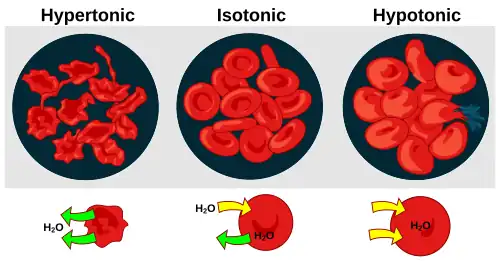

- Physiology